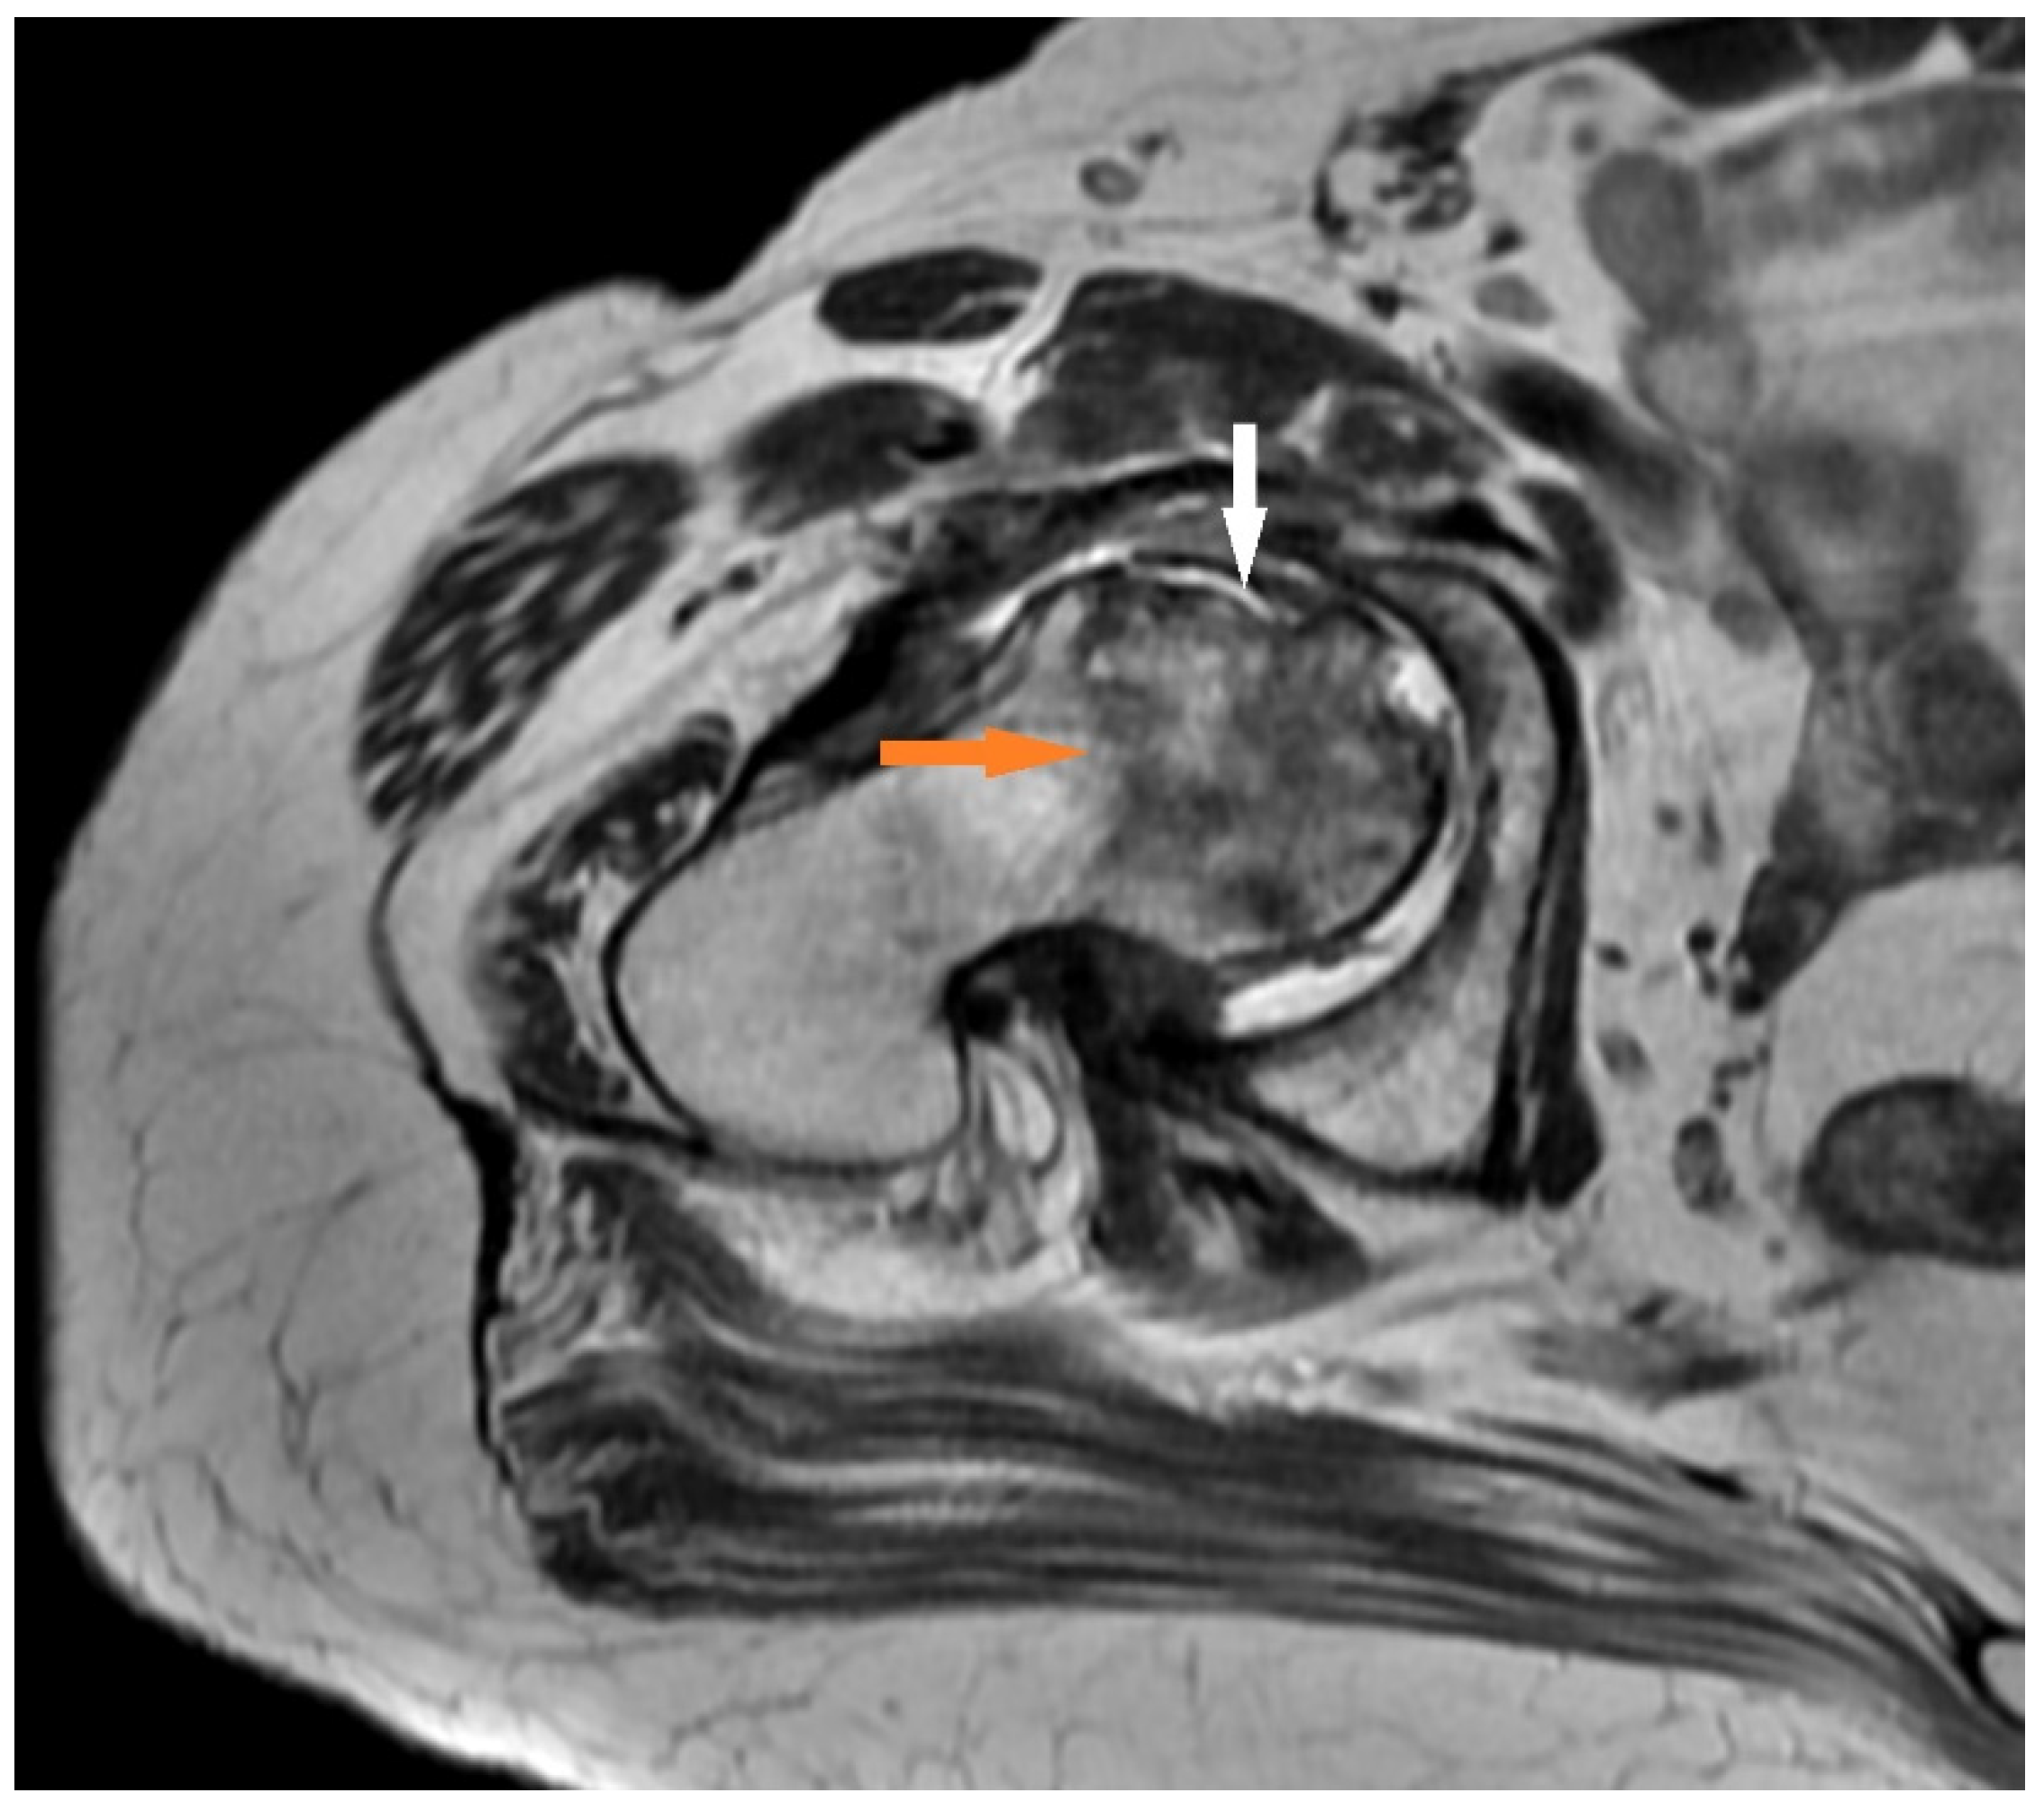

- T2 FR FSE: This may show a second hyperintense inner line between normal marrow and ischemic marrow. This appearance is highly specific for AVN of the hip and is known as the “double line sign”.

3.1.1. Case 1 (Patient No. 5)

3.1.2. Case 2 (Patient No. 1)

3.1.3. Case 3 (Patient No. 7)